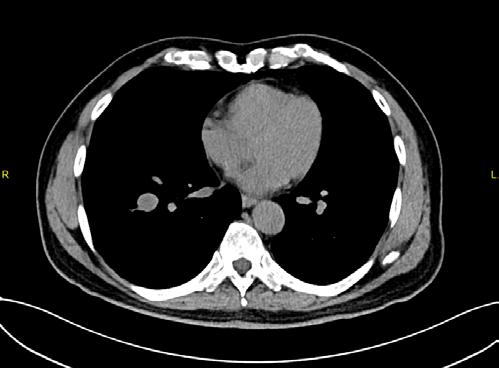

La TC de baja dosis, es la modalidad de imagen más utilizada como método de escrutinio para la detección de lesiones pulmonares, es un estudio rápido, que no requiere preparación previa. ESCANERS DE UN PACIENTE CON

Figura 1-4. Estudio de tomografía simple de tórax, con reconstrucción volumétrica, multiplanares con ventana para pulmón y en mediastino (, en donde se observa el nódulo pulmonar sólido de bordes lobulados hipodensos.

Se presente al caso de un masculino de 80 años de edad que acude por presentar tos en estudio de 3 meses de evolución, sin datos de fatiga, como antecedente de importancia tabaquismo por lapso de 40 años a razón de 1 cajetilla y media diaria (exposición de 60 paquetes año), actualmente suspendido.

Se le realiza estudio de tomografía simple de tórax en donde se encontró en el segmento anterior del lóbulo inferior derecho nódulo sólido, con diámetro de 22mm, volumen de 2.9ml, condiciona disminución del bronquio segmentario, con secreciones endoluminales distales, de acuerdo a la clasificación de LUNG RADS con categoría 4B, alta sospecha de malignidad. Sin evidencia de lesiones nodulares en el resto del parénquima.

Posteriormente, se realiza estudio de PET-CT con 18FDG , con hallazgos de metabolismo asociado y SULmax de 2.0, se recomienda realizar biopsia.

Se realiza cirugía con lobectomía inferior derecha, con resultado histopatológico de tumor carcinoide atípico, se realiza seguimiento con tomografía simple de tórax sin complicaciones en el lecho quirúrgico.